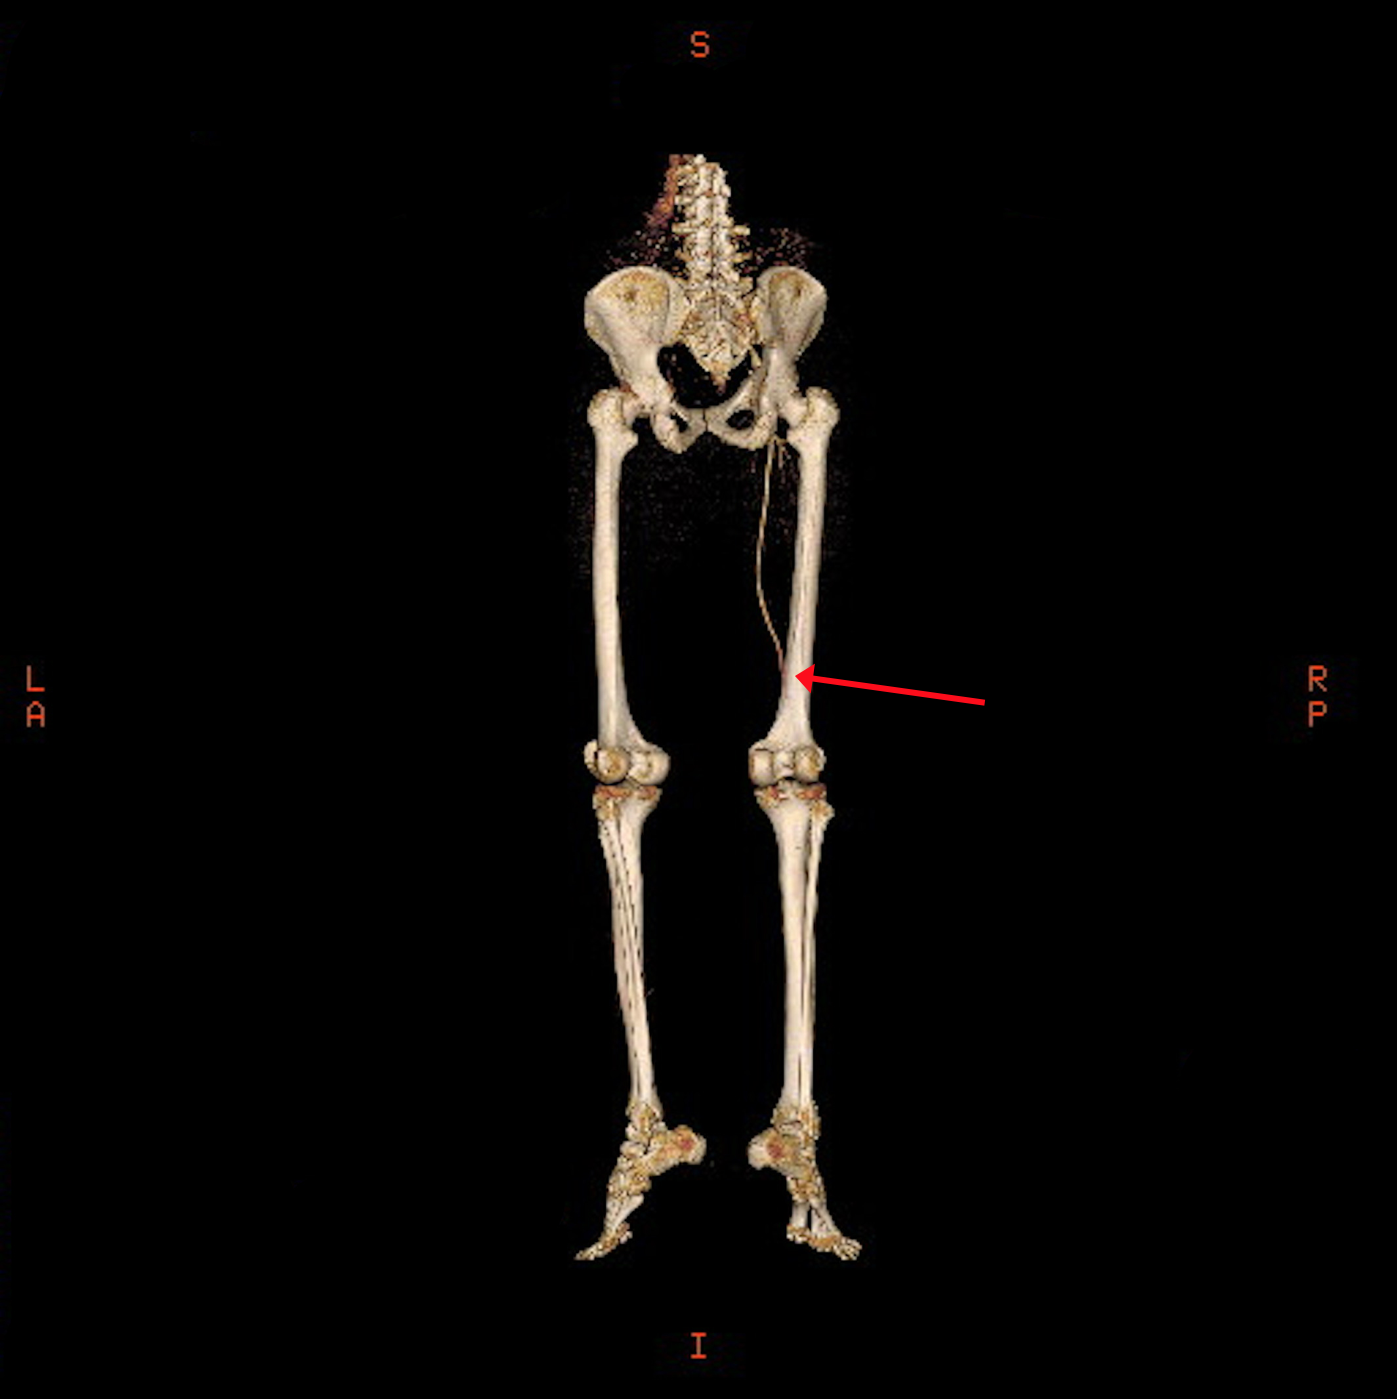

The CT angiogram and CT chest aortogram revealed a hypodense filling defect in the aorta below the level of the renal arteries causing partial occlusion of the aorta (Figure 2). There was complete occlusion of the left common iliac artery just after bifurcation of aorta extending up to the common femoral artery (Figure 3). There was good contrast uptake in right common iliac artery, femoral artery, superficial femoral artery up to the popliteal artery then the abrupt cut off of right popliteal artery present with no contrast filling seen in the distal arteries (Figure 4 and 5). Additionally, multiple bilateral wedge shaped infarcts seen in both the kidneys and the spleen (Figures 6). Chest x-ray was normal.

Figure 3: 3-Dimentional Angiogram showing a complete obstruction of the left iliac artery.

Figure 4: 3-Dimentional Arteriogram showing complete obstruction of the right popliteal artery.